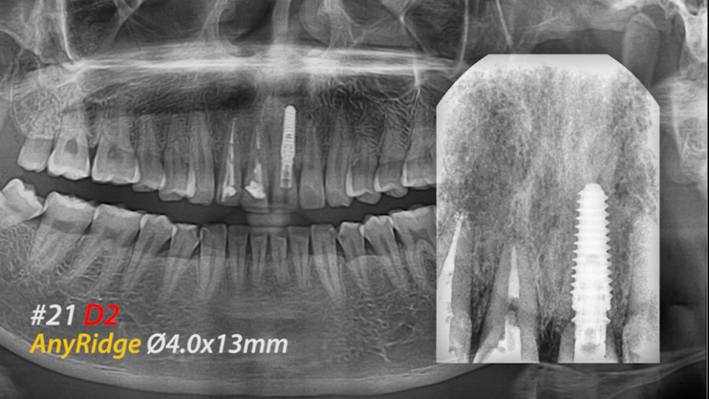

Clinical case: Extraction, immediate placement & loading using

R2GATE solution in aesthetic zone

- Courtesy of Dr. Jong-Cheol Kim, Korea-

Dr. Jong Cheol Kim, immediate loading, digital guided surgery, Digital ONE-DAY Implant, maxillary anterior, #21, guided surgery, immediate loading, AnyRidge, R2GATE, Mega ISQ, MEG Torq, R2GATE Full Surgical Kit

AnyRidge implant system, R2 Guide, R2GATE Full Surgical Kit, Mega ISQ